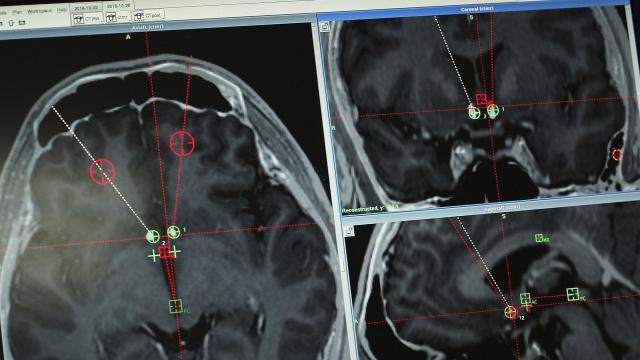

DBS builds on that history. The surgery involves implanting a device that acts as a kind of pacemaker for the brain, electrically stimulating targeted areas. Instead of irreversibly killing brain cells, the devices allow interventions that are — in theory — reversible. The technology has opened a fresh field of human experimentation globally.